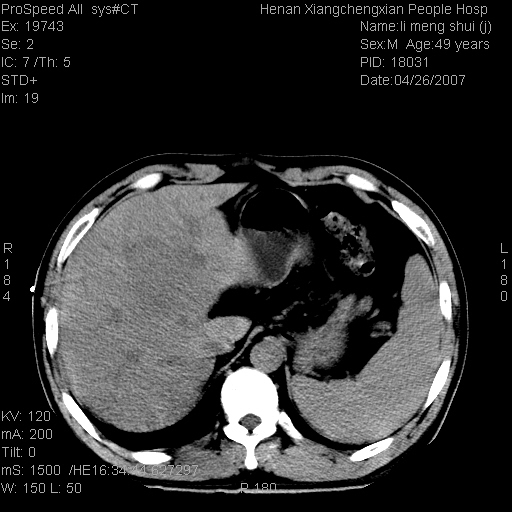

| 患者,男,49岁, 腹疼伴恶心\\呕吐20天,20天前无明显诱因出现右上腹部疼痛,钝疼,无放射,伴恶心\\呕吐,不伴发热.患者不愿增强. b超:肝脏右叶实性占位. ct:肝脏右叶可见一巨块状圆形低密度影,大小约93mm*84mm,其内可见点状高密度影,胆囊、胰腺、脾脏大小、形态及密度未见异常,腹膜后间隙未见肿大淋巴结影。 印象:肝脏右叶巨大肿块,性质待定,建议增强并穿刺活检进一步确诊。 ct平扫: ![]() ![]() ![]() ![]() ![]() ![]() ![]() ![]() ![]() ![]() ![]() ![]() ![]() ![]() ![]() ![]() ![]() 肝脏右叶肿块ct引导下穿刺活检术 患者于16时05分仰卧于ct检查台上,首先行肝脏ct扫描确定进针位置、深度、角度。在局麻下行ct引导下肝脏右叶肿块穿刺活检术。常规消毒、铺巾、局麻。在ct引导下使活检针经右侧腋中线、第9肋间隙垂直胸壁进针90mm,针头进入病变预定位置。在病变预定位置多点、多方向抽取小米样病变组织多块,涂片五张送病理检查。术后穿刺点局部无出血,未出现腹腔积液等并发症。术中及术后患者生命体征稳定,手术于17时10分成功完成。患者安返病房。 穿刺片 ![]() ![]() ![]() ![]() ![]() ![]() ![]() ![]() ![]() ![]() ![]() ![]() ![]() ![]() ![]() ![]() 病理结果肝细胞癌 ![]() 原贴地址:http://www.radinet.com.cn/forum_view.asp?forum_id=4&view_id=24130 ok |